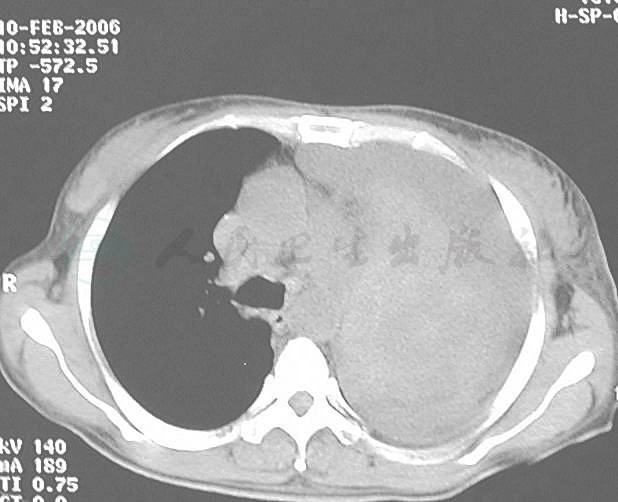

患者,女性,48岁,患2型糖尿病2年,血糖控制不佳。6个月前因糖尿病酮症酸中毒、昏迷入当地医院,予胰岛素等治疗后意识恢复清楚。住院1周时出现发热,体温38℃伴咳嗽,咳痰,查WBC 15×109/L,N 0.80,Hb 120g/L,X线胸片显示左上肺大面积片状渗出影及左侧少量胸腔积液(图1),先后给予左氧氟沙星、克林霉素和头孢哌酮/舒巴坦等抗感染治疗1个月但症状无改善,并出现少量咯血。外院实验室检查:PPD皮试阴性,3次痰查结核菌、真菌培养均阴性,结核抗体阴性,ESR 115mm/1h。曾考虑为肺结核给予异烟肼、利福平、乙胺丁醇治疗1个月,复查胸部CT显示左上肺实变伴空洞形成,洞壁光滑,洞内可见不规则物体(图2),继续抗结核治疗2个月症状仍无改善,并出现大咯血。再次实验室检查显示,WBC 22.7×109/L,N 0.84,Hb 50g/L,X线胸片显示左侧肺野大片高密度阴影(图3),在外院输血、抗结核治疗同时,给予伊曲康唑抗真菌治疗1个月,仍间断出现发热、咯血,并逐渐出现胸闷及双下肢凹陷性水肿,为进一步诊治转入我科。

肺部感染(真菌性肺炎)?肺结核?失血性贫血(重度)、2型糖尿病。入院后实验室检查:空腹血糖11.1mmol/L;HIV抗体阴性;多次痰涂片、痰培养、抗酸染色、痰找真菌等均阴性;G试验、GM试验阴性。动脉血气分析:pH 7.49,PaCO2 37mmHg,PaO2 63mmHg,SaO2 94%;胸腔积液外观黄色,比重1.027,黎氏试验阳性,细胞总数6.72×109/L,有核细胞数0.26×109/L;单核细胞0.94,多核细胞0.06。血生化检查:总蛋白37.0g/L,白蛋白19.2g/L,葡萄糖7.05 mmol/L,乳酸脱氢酶(LDH)188IU/L,腺苷酸脱氨酶(ADA):15U/L。癌胚抗原:4.60μg/L,胸腔积液培养阴性,胸腔积液查结核菌、瘤细胞均阴性。超声心动显示中量心包积液。胸部CT显示左肺实变伴不张,左侧胸腔积液(图4)。

图4 胸部CT显示左肺主支气管开口消失,左肺实变伴不张,左侧胸腔积液,左肺内可见巨大类圆形软组织影(发病6个月)